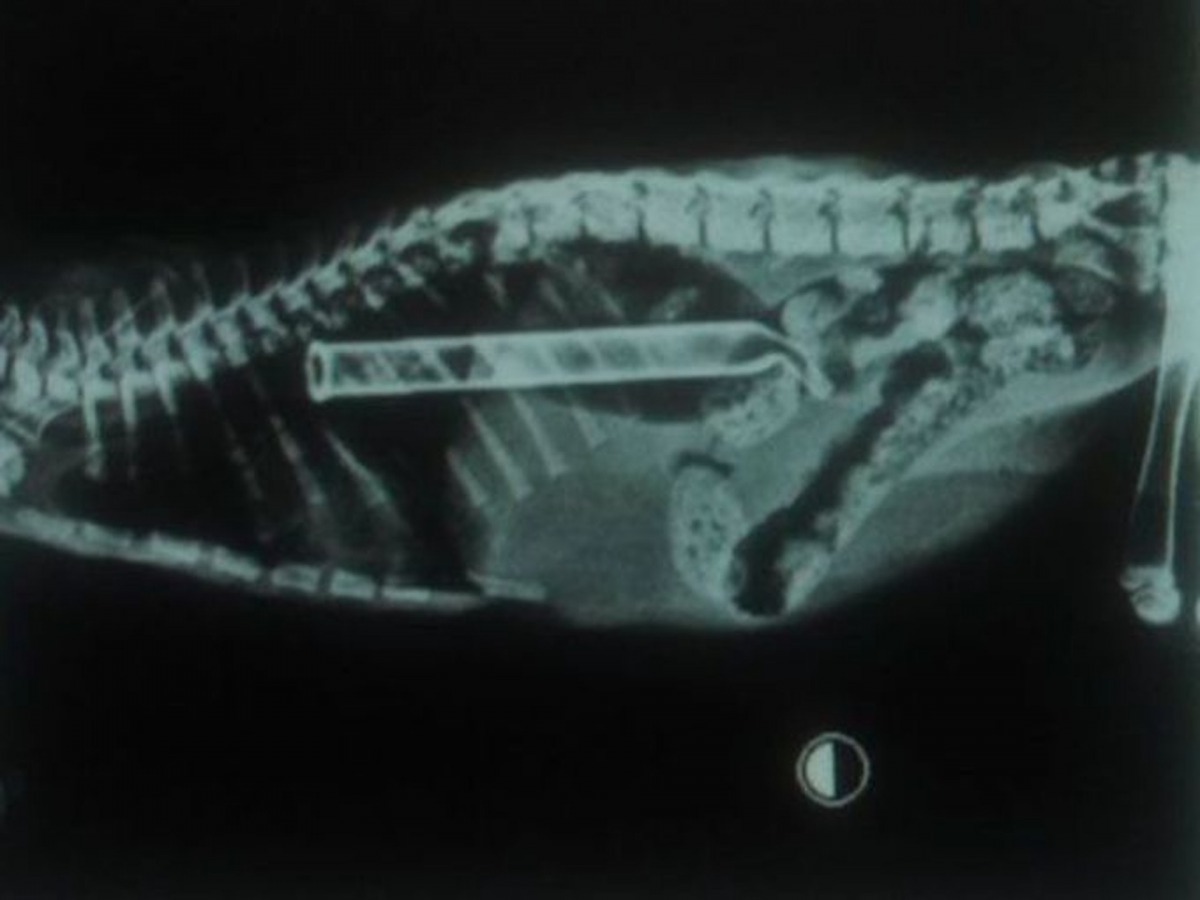

狗狗尤達(Yoda)也不比Marley遜色,牠也成功吞下一個木製「不求人」,更令人驚訝的是,其長度幾乎與牠身軀一樣!還有太多令人驚訝的例子,現在就讓我們一起觀摩一下愛寵們的「創舉」吧!